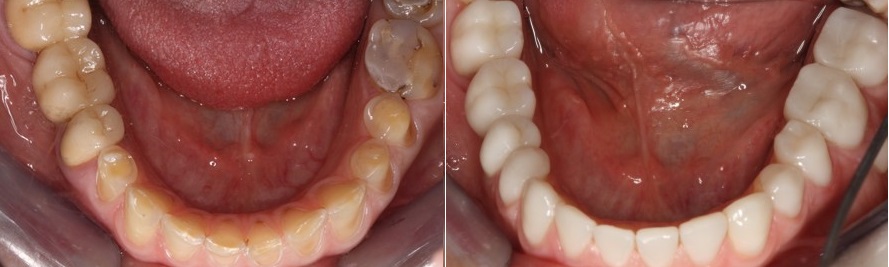

Πολύ εντυπωσιακή είναι και η εικόνα των κάτω προσθίων δοντιών που απεικονίζονται στην φωτογραφία που ακολουθεί, αριστερά.

Διάβρωση δοντιών- θεραπεία

Σε κάθε ένα από τα πρόσθια δόντια, βλέπουμε μια μικρή υπολειπόμενη ποσότητα αδαμαντίνης πολύ κοντά στα ούλα. Παρομοίως στα πίσω δόντια βλέπουμε την αδαμαντίνη που έχει μείνει περιφερικά στην μασητική επιφάνεια των προγομφίων.

Αυτή η μικρή ποσότητα αδαμαντίνης που έχει διατηρηθεί γιατί προστατεύεται από το υγρό της ουλοδοντικής σχισμής, είναι και η βάση του σχεδίου αποκατάστασης που θα ακολουθήσουμε.

Η εικόνα των δοντιών της κάτω γνάθου πριν και μετά την αποκατάσταση